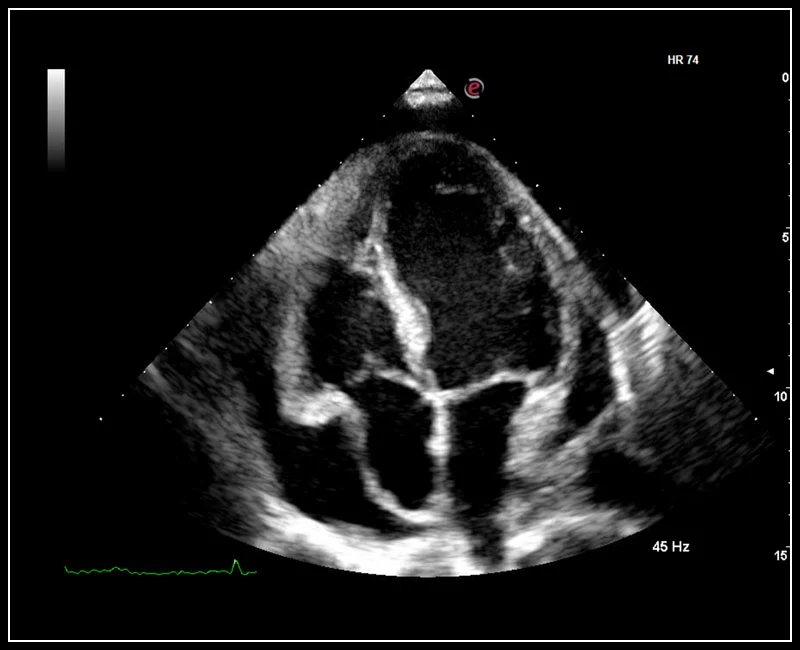

Q7 - CV Cardio B-mode

Q7 - CV Cardio B-mode

Q7 - CV Cardio B Mode 2

Q7 - CV Cardio B Mode 2